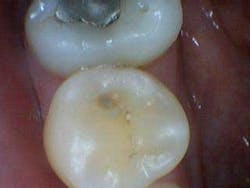

In the aforementioned case, the reading on the occlusal surface was a 46 (see Figs. 3 through 8 below). Look at what was underneath. Surprised? I often wonder how many times per day lesions like this are going undiagnosed.

After the final smear layer was removed, the tooth was filled with Grandio resin. Afterwards, I showed the photographs to my patient. Any doubt that he had was immediately erased. Most importantly, he was grateful and his trust in me was solidified.